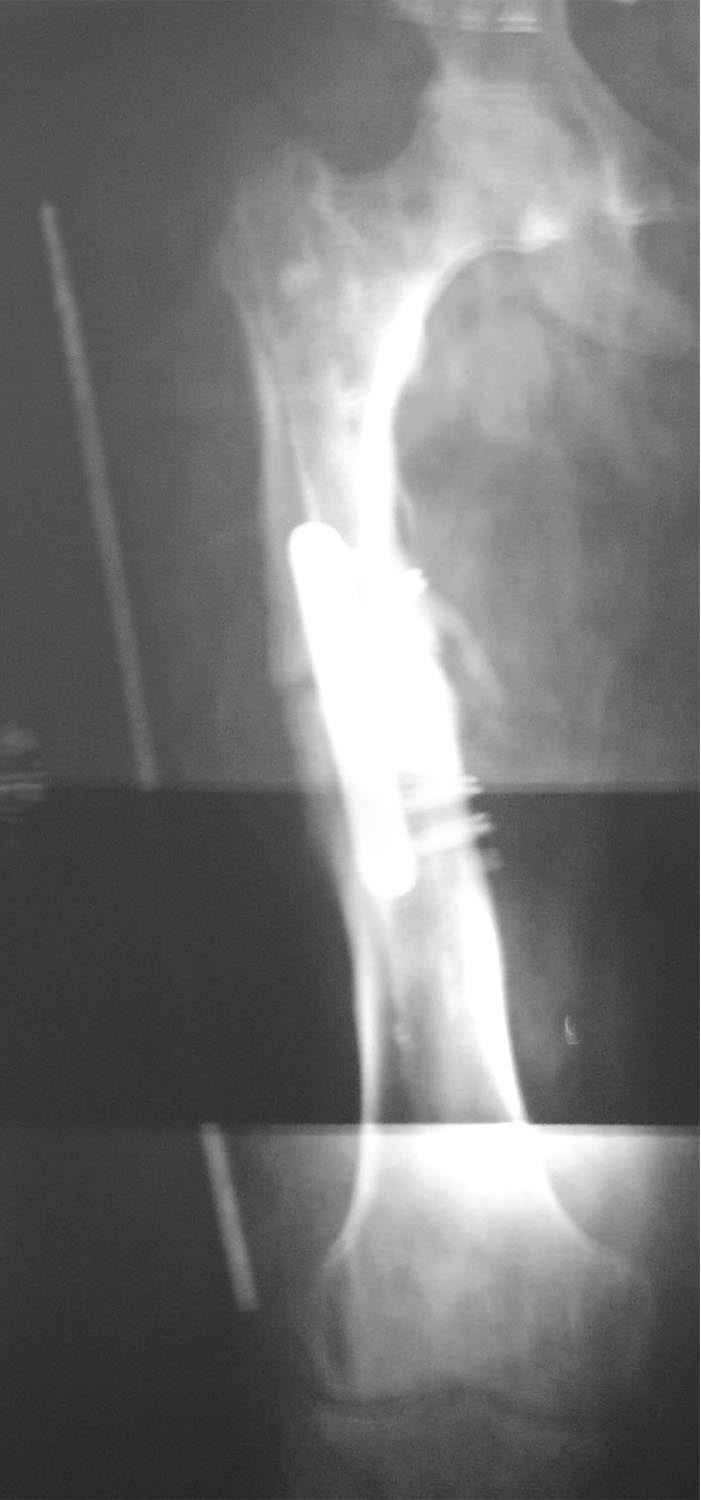

Re: ложный сустав средней трети бедра

укорочение 15мм, клинически варуса нет. в приложении снимок на 2 пленках с центр на суставах, с приклеенной на уровне кости стержнем L-300mm,d-5mm.

Сдается мне, что можно не искать, несращение не околосуставное, так что просто взять стержень потолще, да запереть. Получится с компрессией - хорошо, не получится - просто статически на пару

месяцев, а потом отпереть. Что все-таки решили делать?